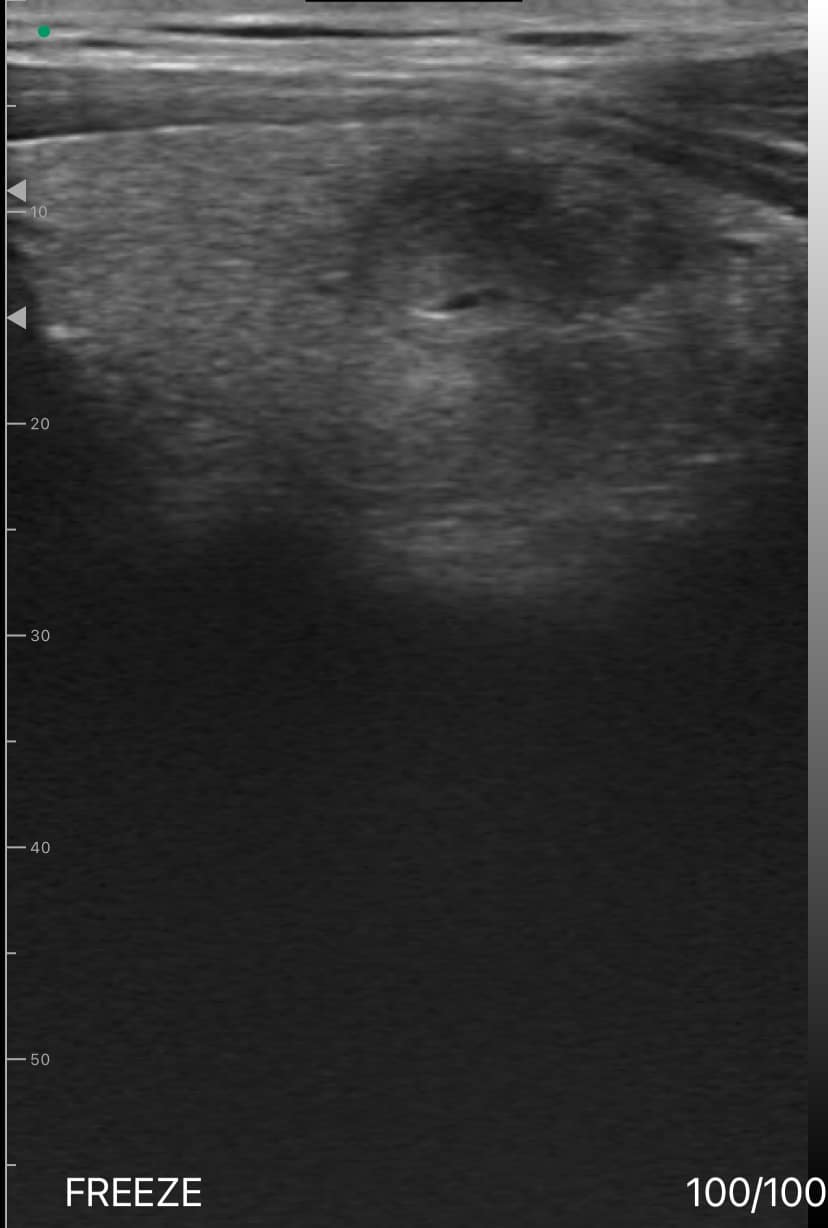

Dr. Emily Thompson, who runs an endocrinology clinic in San Francisco, CA, used the Dr. Sono Tri-Scan Max Portable Ultrasound to evaluate a 45-year-old female patient with a known thyroid nodule and cyst. The patient had been experiencing mild neck discomfort and requested a follow-up ultrasound to assess any changes.

Upon examination, the thyroid nodule measured 1.8 cm and appeared isoechoic with well-defined margins, while the adjacent cyst measured 2.1 cm and exhibited anechoic characteristics with a thin, smooth wall. Color Doppler imaging revealed no significant blood flow in either the nodule or cyst, indicating that both lesions were stable and non-cancerous.

Using Dr. Sono, Dr. Thompson performed additional scans of the surrounding lymph nodes and the contralateral thyroid lobe, which showed no signs of metastasis or new abnormalities. This comprehensive scan helped reassure the patient and allowed Dr. Thompson to monitor the condition effectively without the need for invasive procedures.